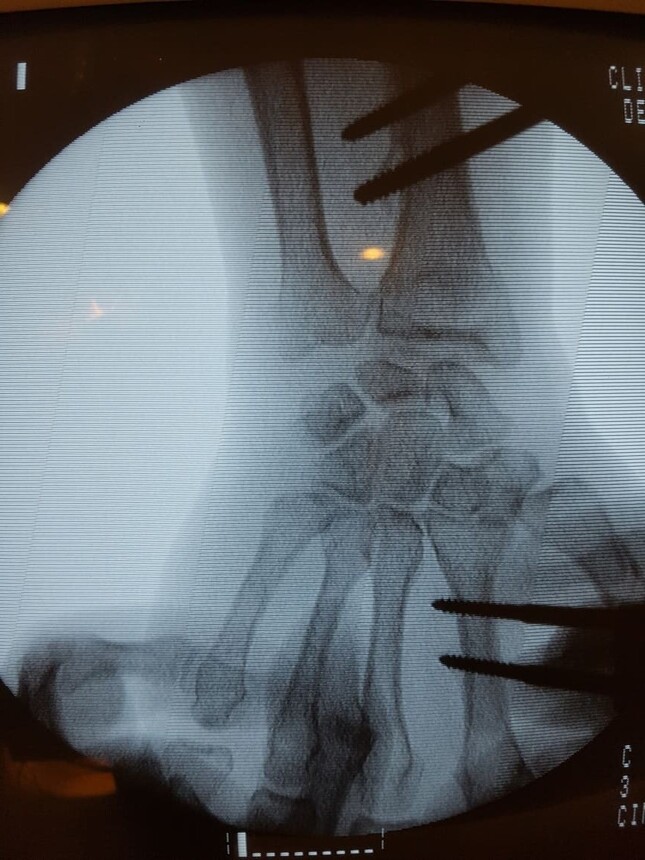

Fractura de radio distal